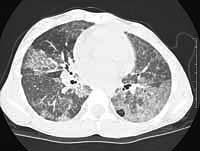

She was treated for viral pneumonia at that time and was noted to have progressively increased oxygen requirements. A high resolution computed axial tomography was done in June 2000, which showed patchy ground glass opacification, prominent azygous lobe "crazy paving" was noted. The exercise test showed that she had difficulty with the test and she had moderate hypoxemia with exercise, desaturation to 80%. Room air oxygen saturation was 89% at rest.

CT

scans: original - after first wash compared to most recent HRCT.

LEFT

CT SCAN (June), RIGHT

CT SCAN (August)